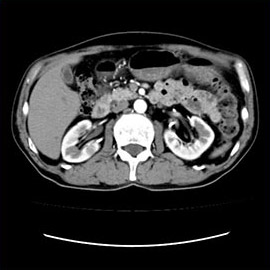

80列マルチスライスCTで撮影した画像

腹部

腹部(造影)

体脂肪計測

1スライスの腹部単純撮影画像から体脂肪面積や皮下脂肪面積を計測し、それぞれの蓄積を観察できます。